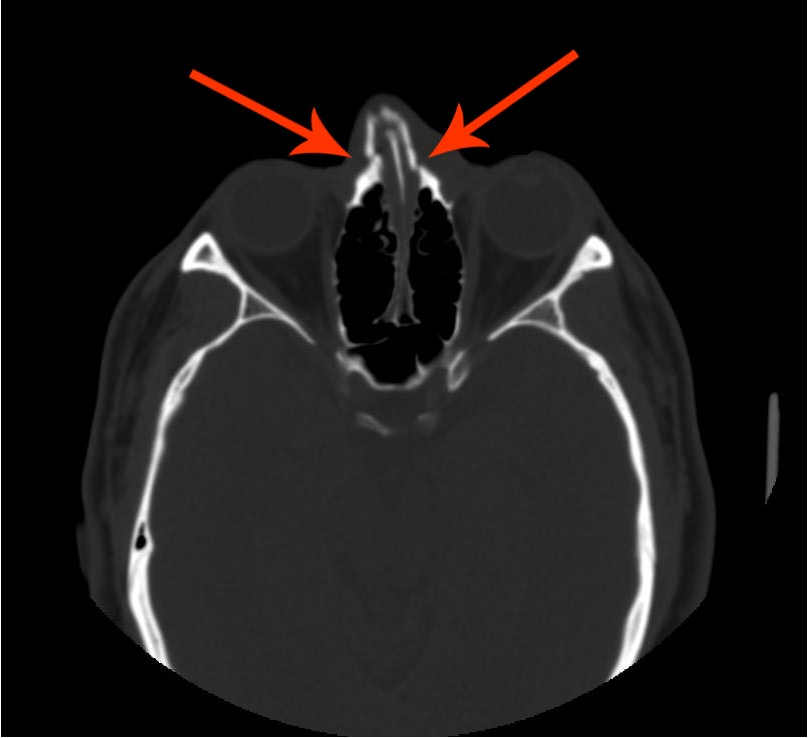

- Fracture nasal bone

- Septal injury

Fracture Nasal Bone